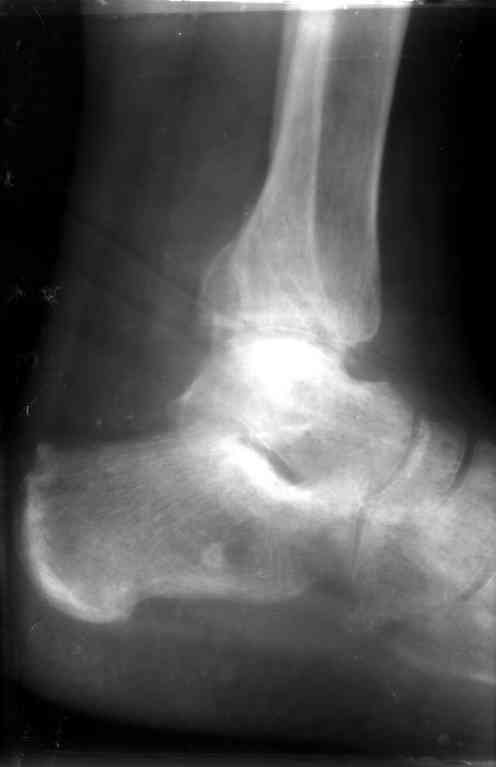

Перелом обеих лодыжек и з/края б/б кости с вывихом стопы,new |

Ув. коллеги, я уже сообщал об этом случае недавно. Металлоконструкции удалены через 7 недель с момента травмы, после чего еще месяц иммобилизации, осторожная дозированная нагрузка. Спустя 3,5 месяцев имеем следующее. Что порекомендуете? С ув. Sergey A. Melashenko ул. Кирова 88-А, г. Приморск, Запорожская обл., 72100, Украина

Ув. Максим. Движения в суставе в полном объеме, беспокоят выраженные боли в суставе, сохраняется отек. Осевая наргрузка болезненна, особенно

в проекции синдесмоза. Похоже вся проблема в синдесмозе. Может обождать, пока окрепнет наружная лодыжка и провести операцию, как при застарелом

повреждении синдесмоза (болт-стяжка или что-нибудь поновее)